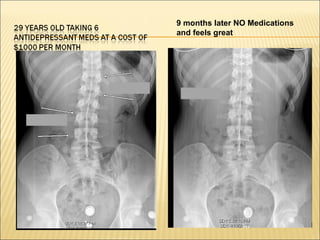

9 months later NO Medications

and feels great

9 months laterNO Medications and feels great